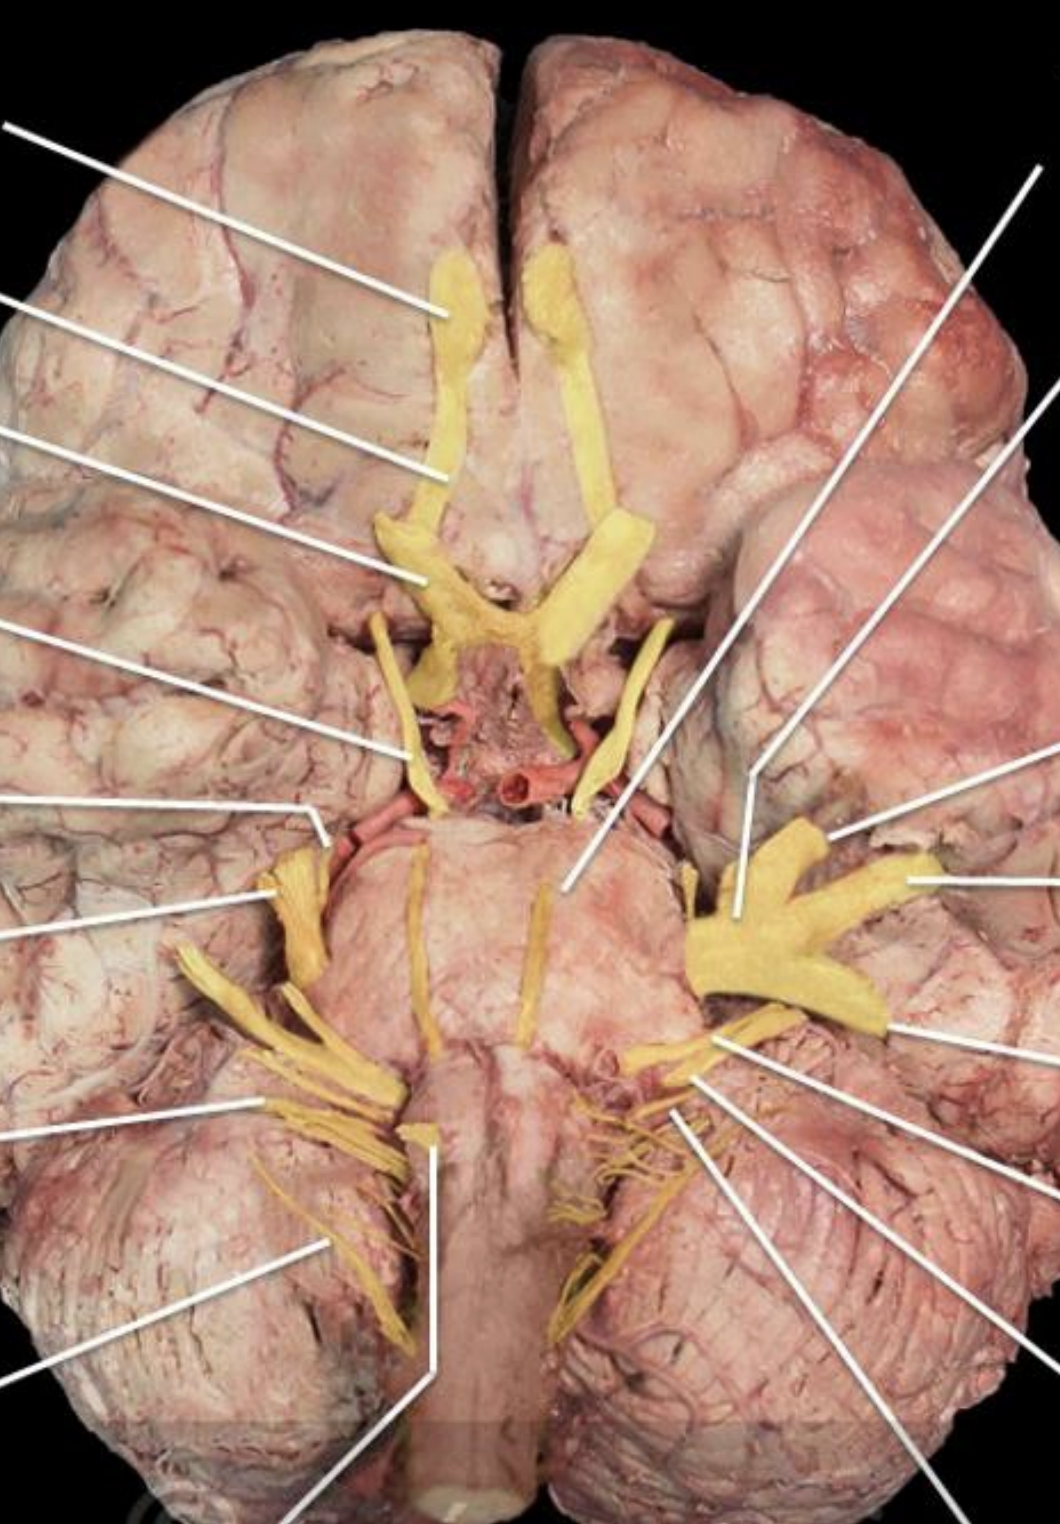

Cranial Nerves